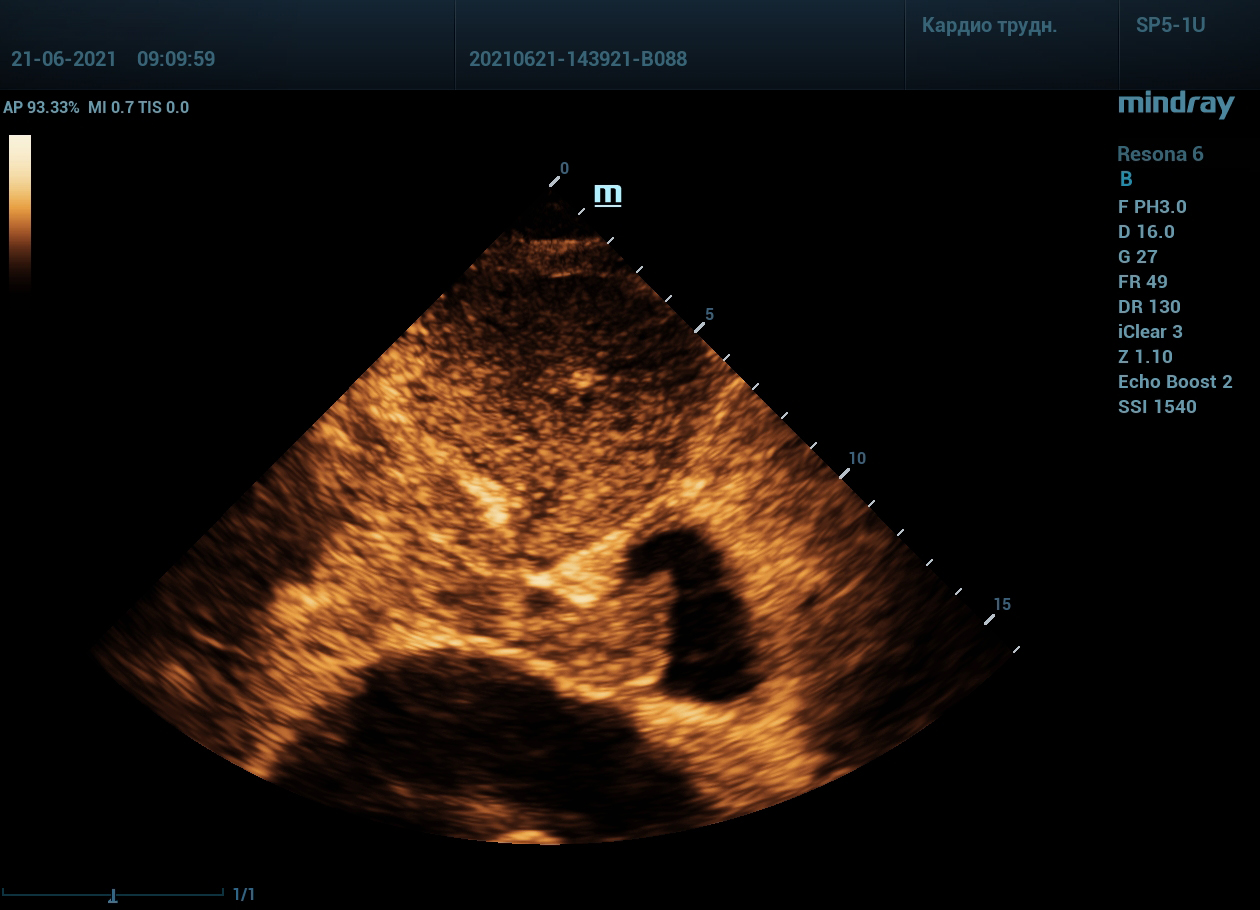

Интересный случай из практики нашего врача-аппликатора. Использовался экспертный ультразвуковой прибор Mindray Resona 6, стандартные заводские пресеты и автоматическая оптимизация iTouch. В эхокардиографии всегда помогает колорайзинг, чаще всего используется оранжевый оттенок. Пациент обследуется перед оперативным лечением по поводу онкологии почки. Вены нижних конечностей у данного пациента без особенностей, сжимаемы и проходимы. Казалось бы, проблема тромбоза миновала но в процессе эхокардиографического исследования, при сканировании нижней полой вены в субкостальном сечении, определяется эхогенное образование. Образование на месте просвета нижней полой вены. Вена расширена, эхогенное включение проникает в правое предсердие. По краю тромба в цветопотоковой визуализации определяется кровоток. Онкологическое заболевание почки осложнилось тромбозом почечной вены, с распространением тромба в нижнюю полую вену и правое предсердие. Изюминку добавляет то, что в других эхокардиографических сечениях тромб совершенно не виден.